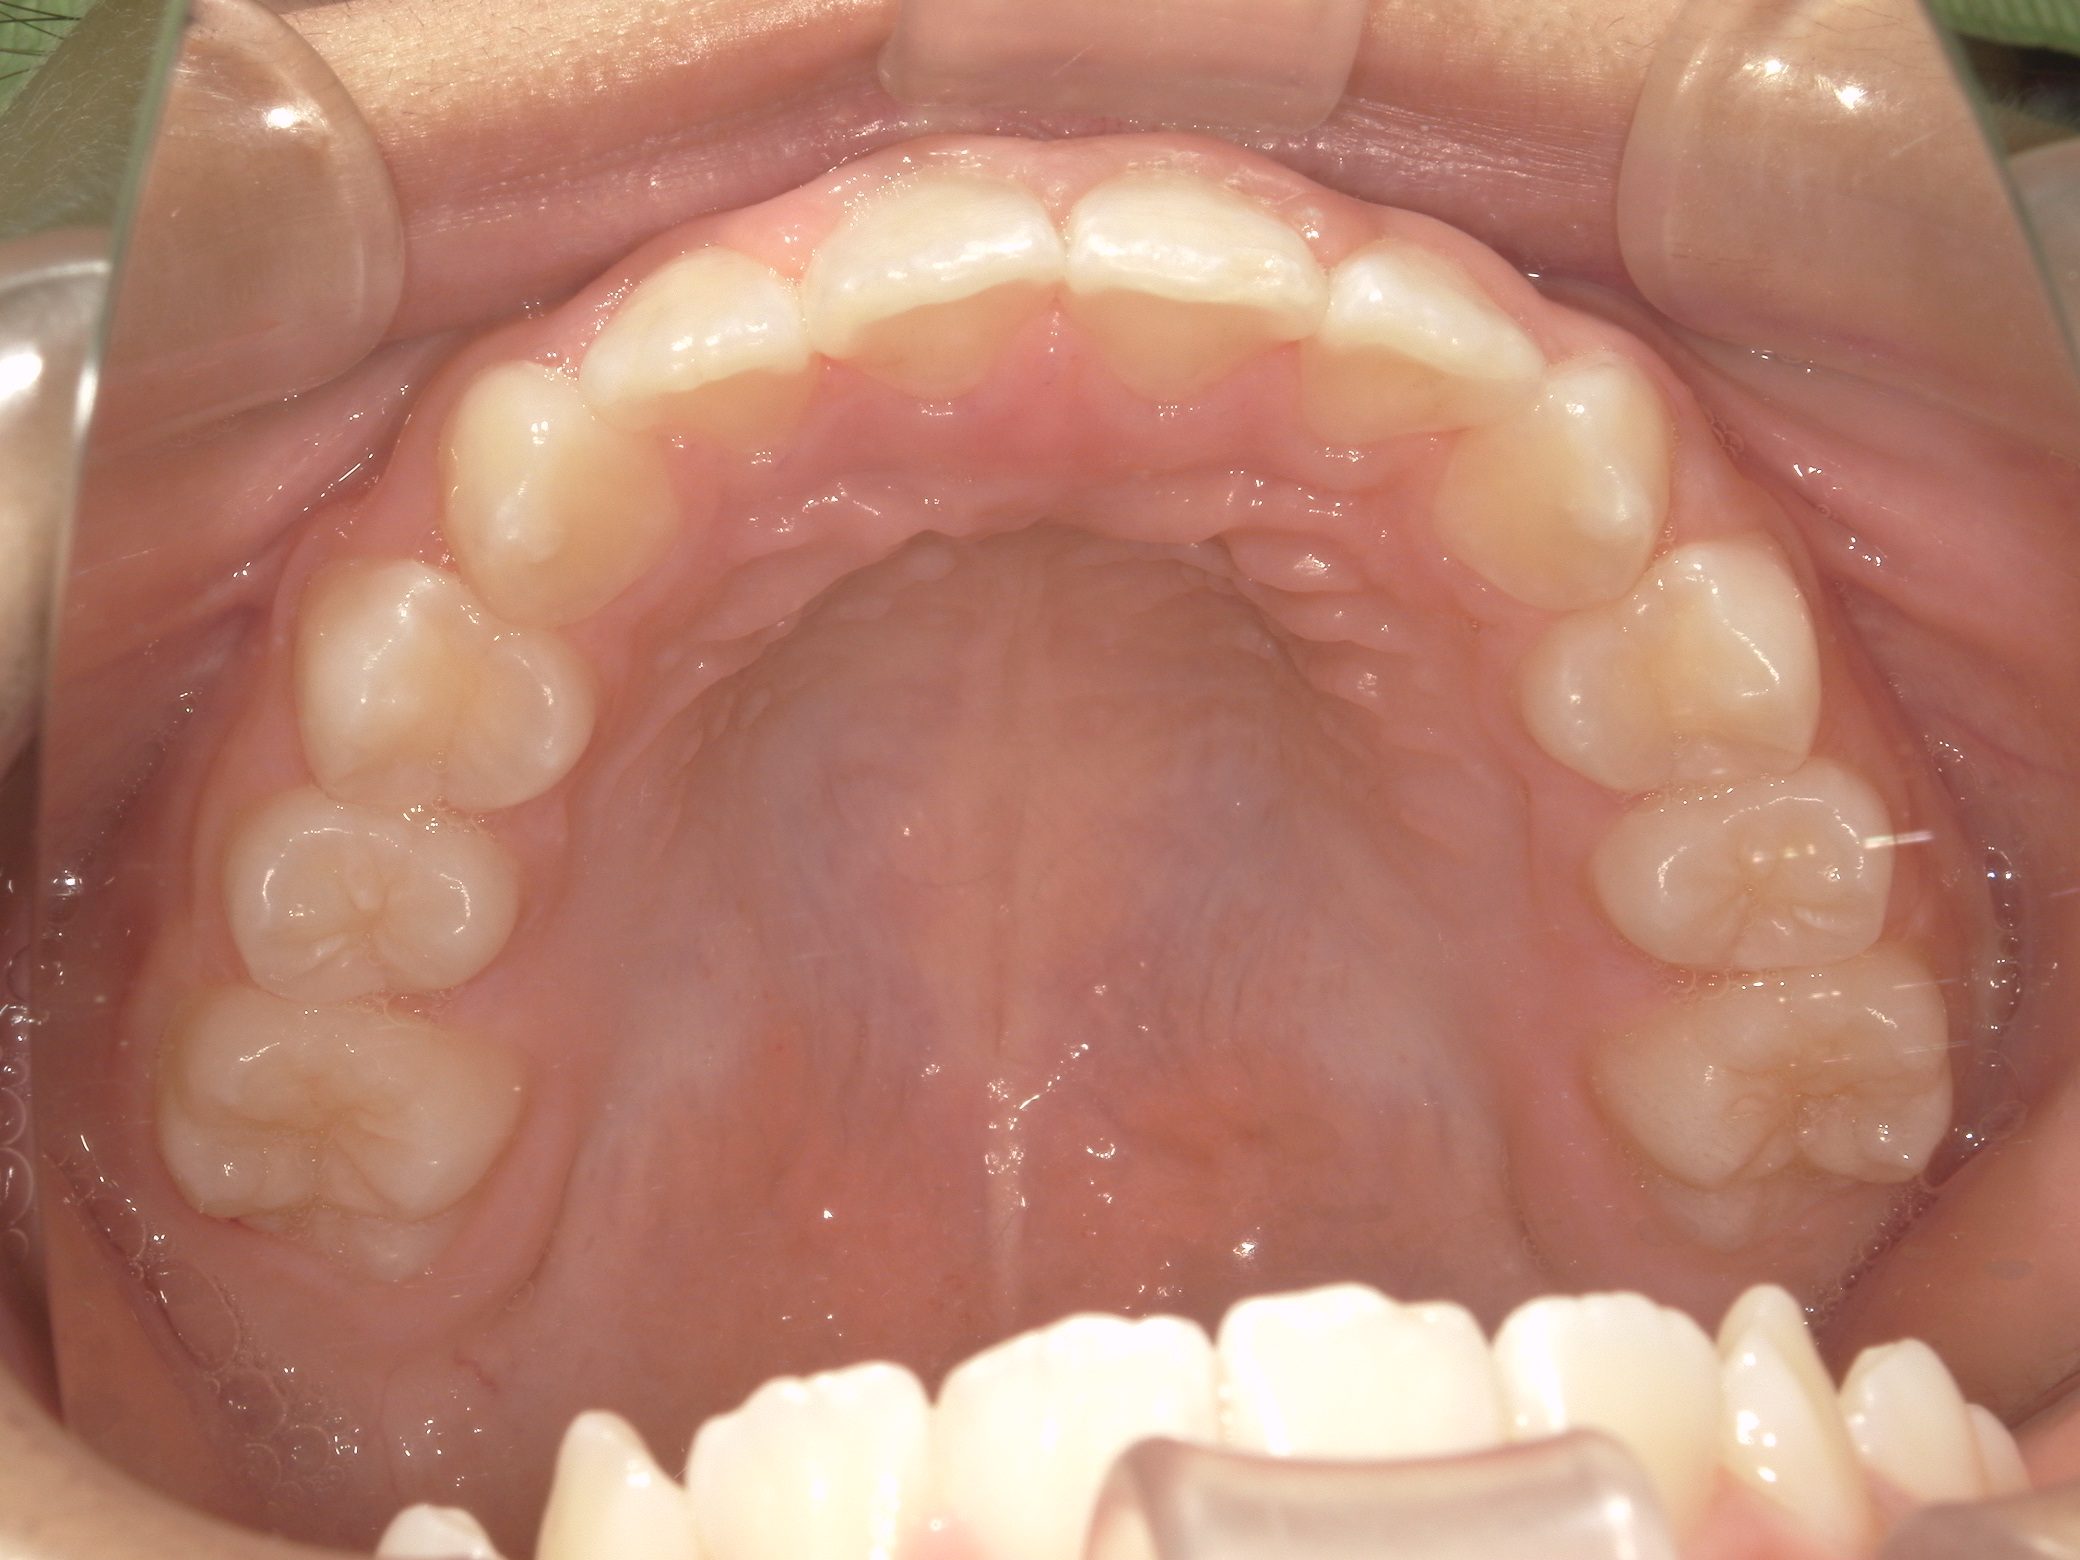

Before

After

【小学生】10歳 マイオブレース矯正 叢生(でこぼこ)と過蓋咬合(深い咬み合わせ)を改善

かなりきちんと取り組んでくれたので、機能矯正装置と MFT(筋機能療法)のみで 改善しています。

機能矯正装置のみで改善するかどうかは もともとの歯並び + 患者さんの装置の使用状況 MFTへの取り組み状況により

変わります。